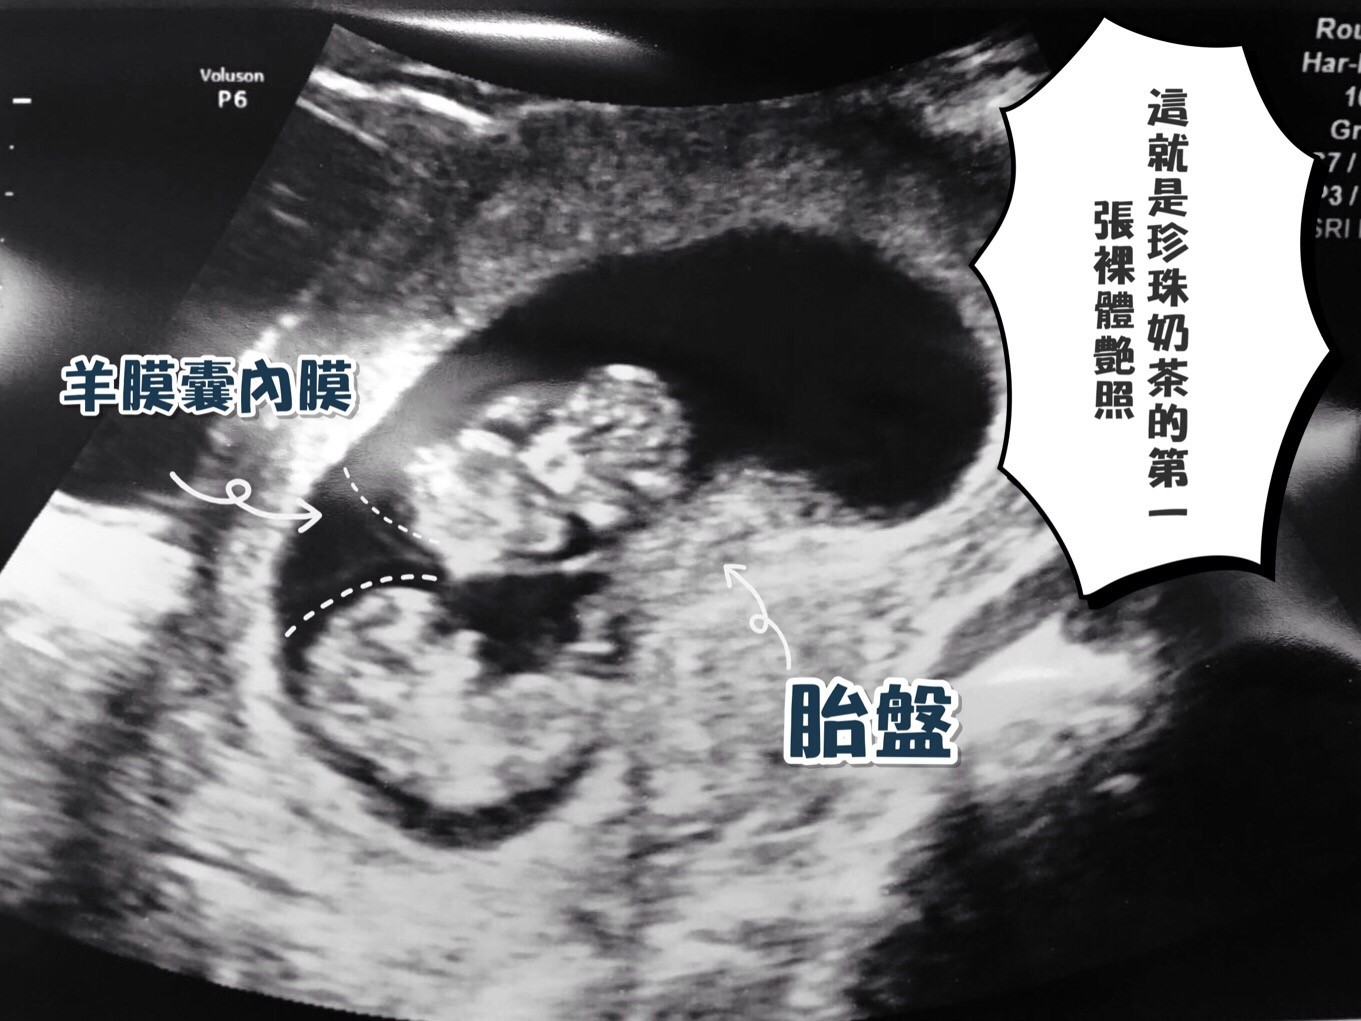

.胎盤 – 連接母親和寶寶的,一面在子宮內側表面,另一面是臍帶供養份給寶寶。

.羊膜囊內膜 – 保護發育中的寶寶,一層薄而堅韌的透明膜包住寶寶同羊胎水。

2. MCDA (單絨毛膜雙羊膜囊)

妊娠危險程度(5*為最嚴重):****

特徵:有一個羊膜囊外膜、兩個羊膜囊內膜分別包住兩個寶寶。兩條臍帶連接住同一個胎盤。

等如:兩個人住在同一間屋,不同的房間。

兩個寶寶,吸收同一個胎盤的養分,因為兩個寶寶的臍帶互相連通,會有很多爭食的情況出現,所以這類懷孕要比DCDA的死亡率高2倍!